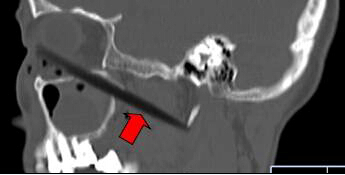

CT顯示筷子還插在腦部

取出的斷筷有9厘米

上周三,62歲的依姆林瓊(化名)在南平家中,有人在揮舞筷子時(shí),將筷子從她右眼眶插入,鼻孔瞬間出血。家人心急,用老虎鉗將筷子外端夾斷,剩下半截筷子嵌在頭面部,之后將其緊急送到福建醫(yī)科大學(xué)附一醫(yī)院。經(jīng)過(guò)1個(gè)多小時(shí)的緊急手術(shù),9厘米長(zhǎng)的斷筷被取出,由于筷子未插中眼球,患者眼睛未受影響。附一醫(yī)院耳鼻喉科副主任醫(yī)師張暉萍提醒,千萬(wàn)不可自行強(qiáng)拔已插入體內(nèi)的物體。傷者被送到附一醫(yī)院時(shí),醫(yī)生幾乎都看不到筷子了。在醫(yī)生的詢問(wèn)下,家屬這才說(shuō),當(dāng)時(shí),他們一心急,用老虎鉗將筷子外端夾斷。這下棘手了。若筷子是完整的還容易拔出,這下完全埋在眼眶下,可怎么取出?影像學(xué)檢查顯示,筷子就靠近視神經(jīng)管、頜內(nèi)血管分支,末端位于頸部大動(dòng)脈的前方。手術(shù)稍有不慎,就可能大出血。為了取出斷筷,附一醫(yī)院耳鼻喉科、頜面外科、眼科、影像科馬上聯(lián)合會(huì)診,擬定了三套手術(shù)方案。第一方案,從插入口直接拔;第二方案,從鼻腔??;第三方案,鋸開眼眶取斷筷。最終,大家選擇了第一方案,因?yàn)閯?chuàng)傷最小,由耳鼻咽喉科張暉萍副主任醫(yī)師和眼科朱學(xué)軍主任醫(yī)師聯(lián)合急診手術(shù)。醫(yī)生們先從眼眶內(nèi)切開傷口1厘米,才看到筷子斷端,順著原先插入口,在鼻窺鏡的幫助下,邊夾邊推,將筷子順利取出。取出的竹筷長(zhǎng)達(dá)9cm,周圍有大量膿液。經(jīng)過(guò)多日抗感染治療,前日,老人才出院。